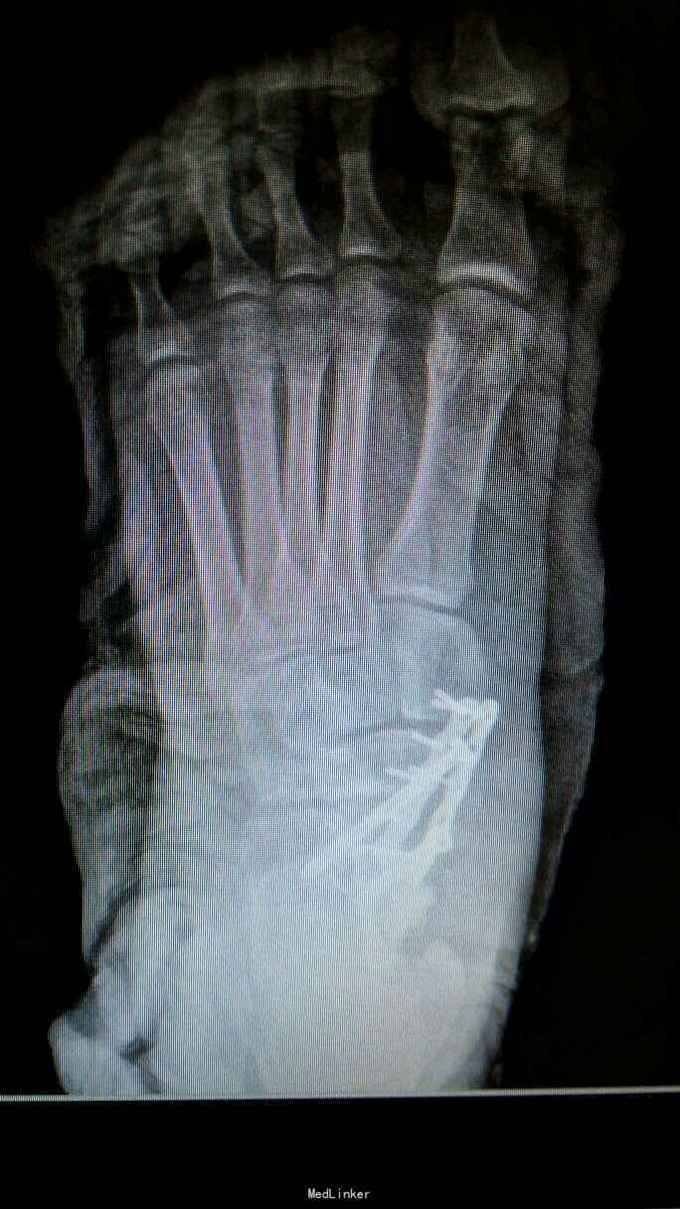

距骨骨折并脱位

重物砸伤左足疼痛畸形14小时。

左踝至中足肿胀,左足内翻畸形,皮肤可见少许细小水泡,压痛,足背动脉搏动可,足趾活动可,感麻木。

距骨骨折并脱位 入院行闭合手法复位失败,予以跟骨牵引5天,石膏外固定3天,皮肤水泡、肿胀消退后行,距骨骨折脱位切开复位内固定+距舟关节融合。术后支具外固定,勿负重3个月。